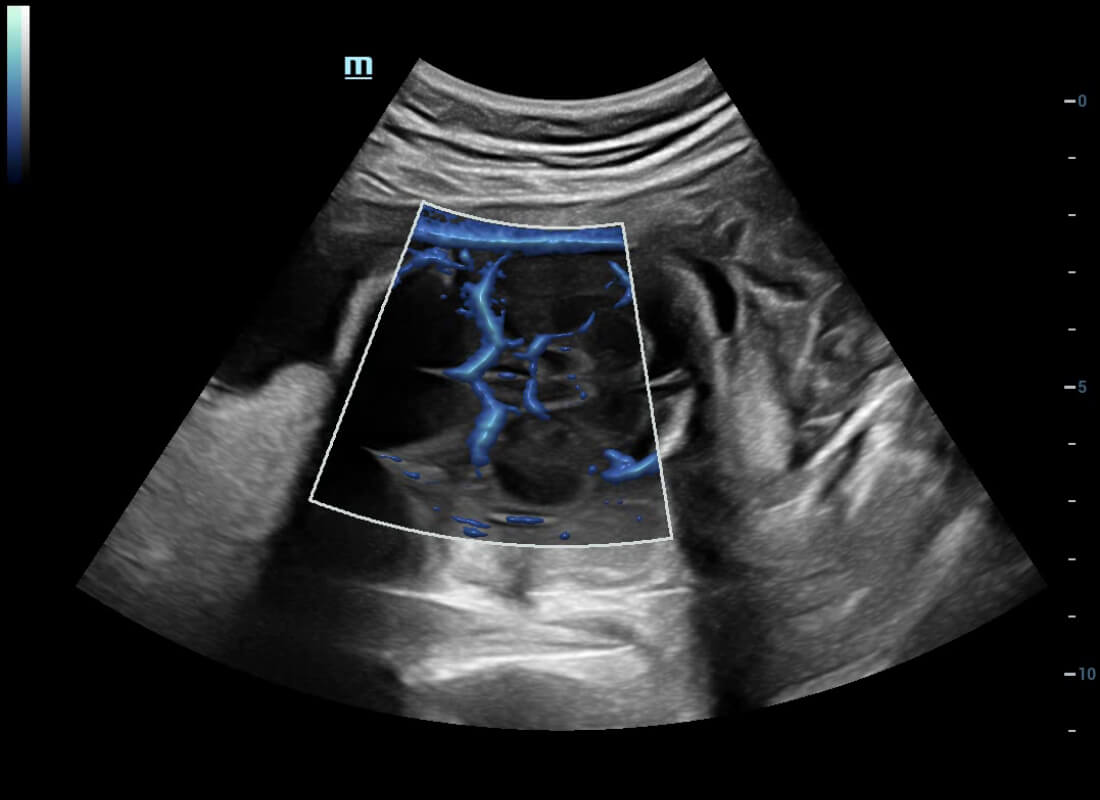

Central nervous system (CNS) malformations are one of the most common congenital abnormalities. Unfortunately, due to imaging limitations such as poor fetal position, acoustic shadowing, and operatorsŌĆÖ poor scanning skills, the MSP is particularly difficult to find in a 2D ultrasound. In this case, a faster and more user-friendly method, which automatically displays the standard planes together with the required measurements in a fetal CNS examination, could significantly boost both the quality and efficiency of clinical diagnoses.?NuewaŌĆÖs intelligent solution of fetal brain can realize automatic acquisition of brain volume data based on intelligent recognition of CNS application scenarios, intelligent generation of four fetal brain standard planes including MSP, automatic measurement of CNS biological items and automatic evaluation of fetal brain volume. More importantly, Nuewa's leading color Doppler technology can provide a clear and sensitive dynamic display of blood flow in the tiny vessels.